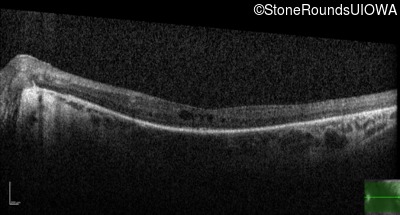

Optical Coherence Tomography - Right - 20/60 -1

Exemplar / OCT Stack